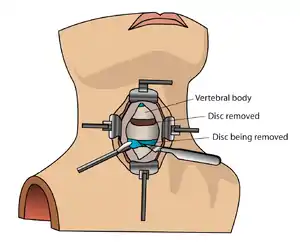

The neurosurgeon or orthopedic surgeon enters the space between two discs through a small incision in front (= anterior) of and at the right or left side of the neck. The disc is completely removed, as well as arthritic bone spurs. The disc material, pressing on the spinal nerve or spinal cord, is then completely removed. The intervertebral foramen, the bone channel through which the spinal nerve runs, is then enlarged with a drill giving the nerve more room to exit the spinal canal.

To prevent the vertebrae from collapsing and to increase stability, the open space is often filled with a graft. That can be a bone graft, taken from the pelvis or cadaveric bone; or an artificial implant.[4] The slow process of the bone graft joining the vertebrae together is called "fusion". Sometimes a titanium plate is screwed on the vertebrae or screws are used between the vertebrae to increase stability during fusion, especially when there is more than one disc involved.